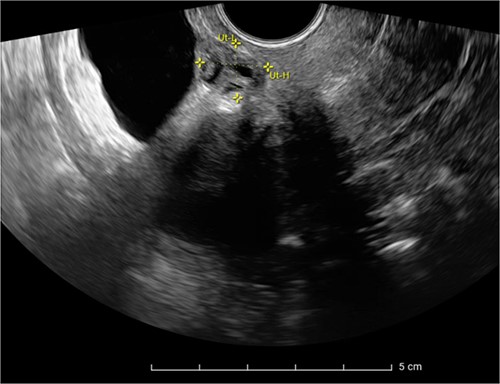

The patient was planned for a robotic resection of the endometriosis nodule and hysterectomy by an experienced robotic gynecological surgeon. The patient was placed on a PinkPad (Kebomed Europe AG) in a lithotomy position. Cystoscopy was performed with placement of ureteral stents. Double-J stents were guided up to the kidneys. Instillation of 200 ml physiologic water with 2 cc of ICG (1.9 mg/cc) in an empty bladder, with subsequent clamping of the urinary catheter (Fig. 3). The da Vinci Xi robot platform (Intuitive Surgical Inc.) was used. Instruments used were: bipolar fenestrated forceps, unipolar scissor, Cadière forceps, and Vessel Sealer Extend. Circumferential incision, dissection and detachment of the endometriotic nodule from the posterior bladder wall was performed under guidance of NIR imaging and ICG, whilst the endometriosis nodule remained stuck on the uterine isthmus (Fig. 4; Supplementary Video). During the dissection, perforation of the bladder mucosa could be avoided, with transparency of the bladder mucosa by ICG. During the hysterectomy part, the bladder catheter was unclamped. The posterior bladder wall was repaired longitudinally. The muscular layers and serosa of the bladder were sutured with Monocryl 3/0 in a two-layer closure (Fig. 5). The bladder was filled with 200 cc of physiologic water with ICG, no bladder leakage nor clear transparency by ICG of the posterior bladder wall was seen. The total operative time was 120 min. The total blood loss was 25 mL. There were no perioperative complications. The length of the hospitalization was 48 hrs. Oxybutynin was given to prevent bladder spasms from the urinary catheter and/or stents. The Foley catheter was removed after 9 days, and the ureteral stents removed after 10 days. At the 2-week outpatient visit the patient was satisfied, and didn’t experience any pain nor urinary voiding problems.

Bladder filled with physiologic water and ICG with subsequent clamping of the urinary catheter.